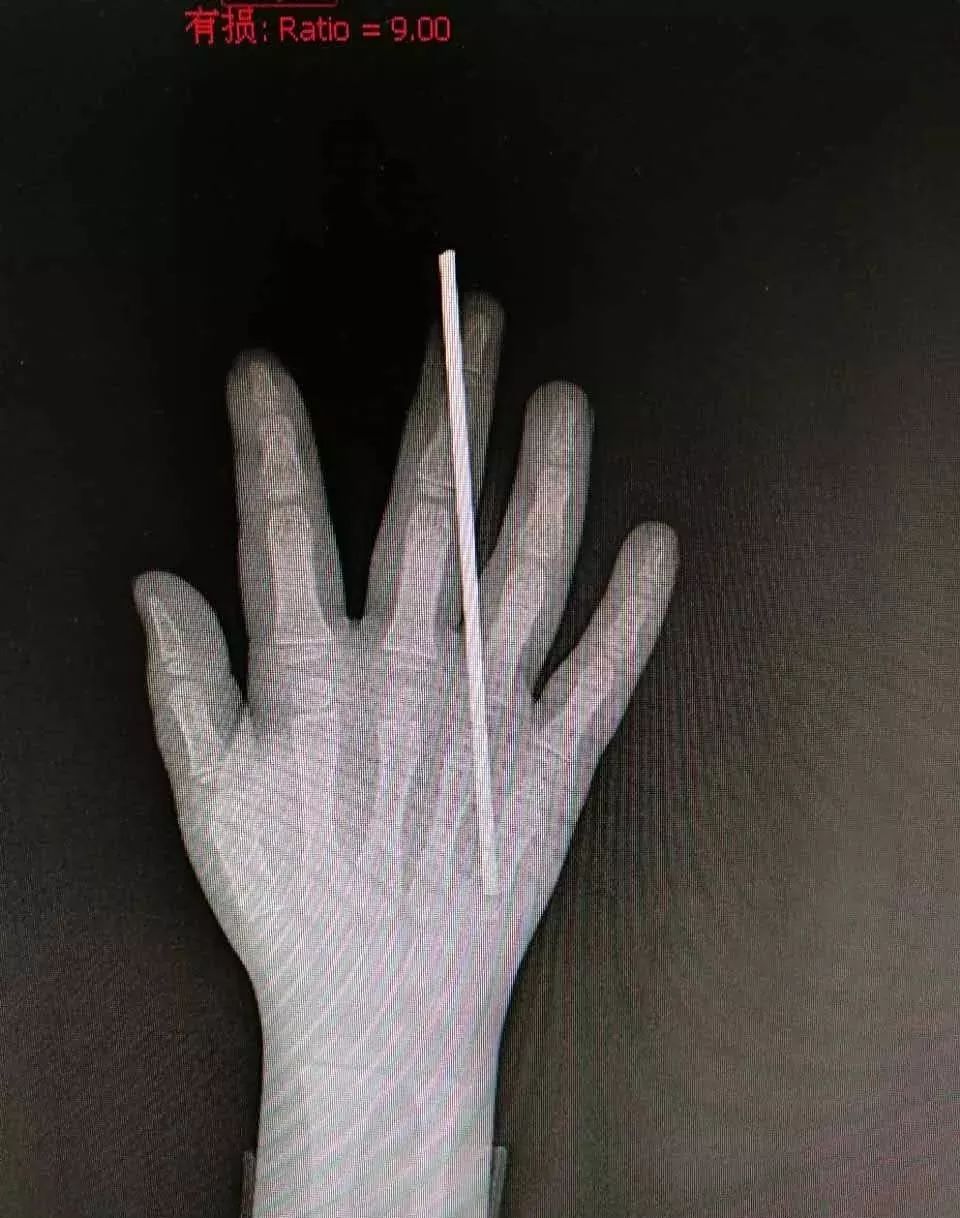

钢丝刺穿孩子中指

在武汉儿童医院,小石头很快进行了手术,钢丝从中指第二指节斜插,刺穿了指头,医生将钢丝取出后,仔细清理了伤口、探查肌腱,万幸的是肌腱并未受损。

心有余悸的王先生说,听邻居讲,出事时小石头一直在墙边上玩钢丝,墙上这根钢丝伸出来大约20多厘米,小石头不停跳起来用手拍钢丝,钢丝摆动孩子玩得很开心,没想到乐极生悲,拍到正在摆动的钢丝头,立即刺穿了小石头的手指,孩子表示再也不敢调皮了。